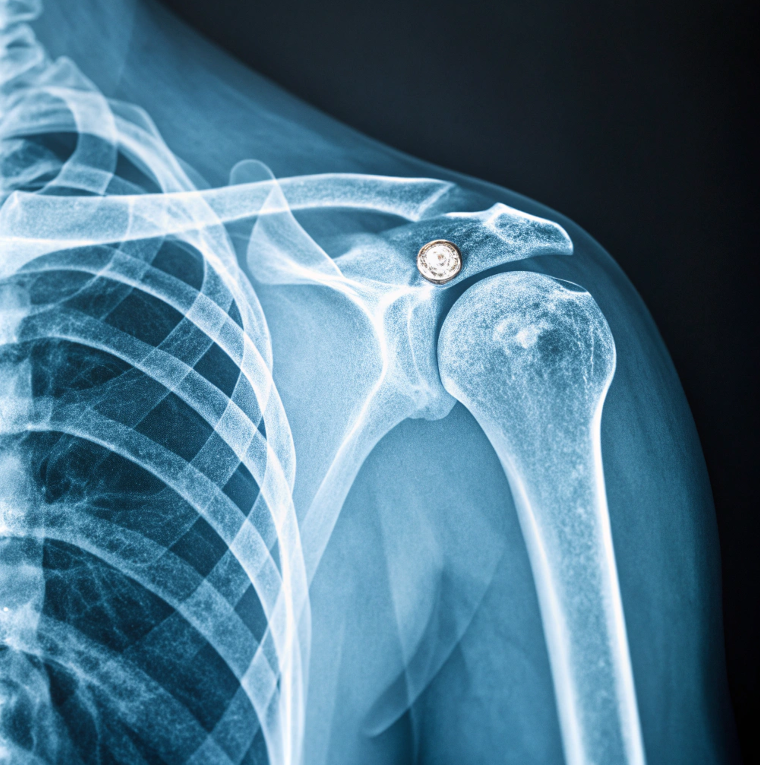

Во время очередного заезда Илья не вписался в резкий поворот. Скорость была небольшой, но падение оказалось неудачным — удар пришёлся на плечевой пояс. Боль была сильной, пришлось обращаться за медицинской помощью.

Врачи диагностировали повреждение связок и подозрение на перелом, поэтому назначили ряд обследований, включая рентген. Сам пострадавший не переживал — здоровье у него крепкое, серьёзных проблем раньше не было.

Через несколько недель восстановление шло по плану. Однако врач-рентгенолог, изучая снимки, заметил необычное включение в кости плеча. По форме и плотности оно напоминало металлический объект размером около нескольких миллиметров.

Специалист предположил, что это может быть старый фрагмент дроби или шарик, который каким-то образом оказался внутри много лет назад и со временем полностью оброс костной тканью. Проблема заключалась в том, что сам Илья не мог вспомнить ни одного случая, который мог бы привести к такому результату.

Операция прошла быстро. Через пару дней Илью выписали. На память он попросил показать извлечённый объект — маленький металлический шарик серого цвета, без следов коррозии.

Через несколько недель, уже из чистого интереса, мужчина снова сделал рентген. Результат оказался ещё более загадочным - объект снова находился внутри тела, но уже в другой кости. При этом вокруг него снова начала формироваться костная ткань.